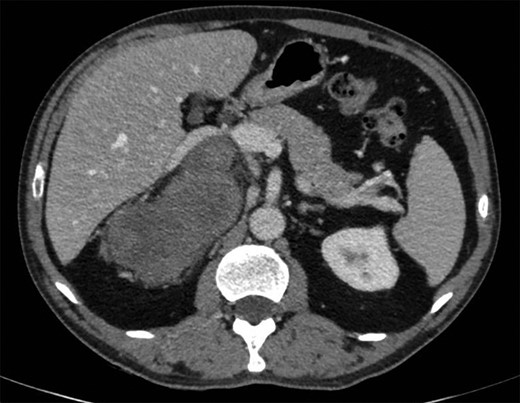

A 57-year-old man was admitted following the accidental discovery of a large mass in the right hypochondrium, detected during an ultrasound examination performed in the context of an assessment of urethrorrhagia. When questioned, the patient reported, with hindsight, upper body cyanosis in anteflexion. A CT scan showed a right-sided retroperitoneal mass measuring 100 × 165 × 164 mm, pushing the liver and right adrenal gland forward, with the inferior vena cava narrowed and pushed forward in the same way (Fig. 1). A cleavage plane was described with all the adjacent structures (liver, kidney, inferior vena cava). The mass was encapsulated, well circumscribed, trilobed, of tissular appearance, with spontaneous density of 35 UH, heterogeneous, containing liquid portions of necrotic appearance and two punctiform calcifications. After injection of the contrast product, there was moderate and heterogeneous uptake of the mass in late portal time (+10 min).